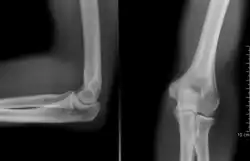

![]() Radiografía del codo. | ||